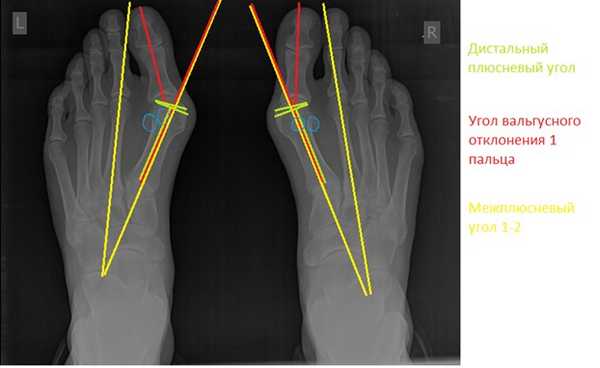

Хирургическая тактика обсуждается с пациентом. Разъясняются особенности хирургического доступа, анестезиологического пособия, последующей реабилитации. Эту пациентку беспокоила деформация только 1 луча, вмешательства на 2-3-4-5 лучах стопы не потребовались.

Через 6 недель выполняются контрольные рентгенограммы, если на них всё в порядке, то разрешается ходьба с нагрузкой на передний отдел стопы. Также на этом этапе целесообразно выполнение ЛФК и физиотерапевтических процедур направленных на дальнейшую разработку движений в 1 плюсне-фаланговом суставе.